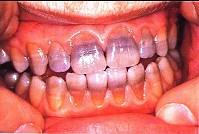

问题 关于四环素牙,下列哪—项错误()

选项 A.四环素可通过胎盘引起乳牙着色 B.四环素对牙的影响仅仅是着色,影响美观 C.通常前牙比后牙着色深 D.四环素在牙本质中的沉积比在釉质中高4倍 E.四环素牙的着色是永久的

答案 B